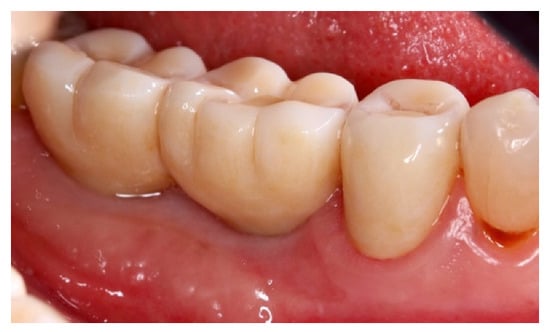

The surgery protocol was the same as described in the previous case (Figure 11a–e). The extraction of teeth and the simultaneous insertion of the implants was performed in the same session (Figure 11a). The enriched clot (1 g beta-tricalcium phosphate for every 5 mL of clot) was protected by the shaped foil fixed with screws (Figure 11b) and its successive removal was at six months (Figure 11c). A further six months were necessary for soft tissue maturation (Figure 11d,e). In this case, the flap of keratinized mucosa, indicated by the white arrow in Figure 11c–e, contributed to the stability of the keratinized mucosa. At the follow-up, the gingival tissue was adequately matured, avoiding further graft of soft tissue (Figure 12).

Figure 11.

(a) Avulsion of the teeth and simultaneous insertion of the implants; (b) Use of the enriched clot and cover with the foil blocked with the screws; (c) Removal of the foil at six months; (d) Maturation of the tissues after one week from the withdrawal of the foil; (e) pre-prosthetic situation of implants and mucosa.

Figure 12.

Prosthetic finalization of the case and mucose quality.